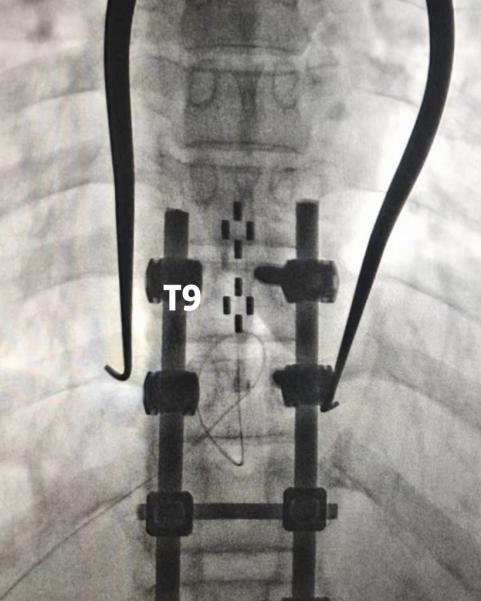

脊髓电刺激选用2-4-2触点排布的片状电极(外科电极),分别植入T8-T9以及T12-L1节段,术中结合影像并通过开启刺激诱发出特定部位的肌电,来确定上方电极位置的准确性。

图片图片

术中影像